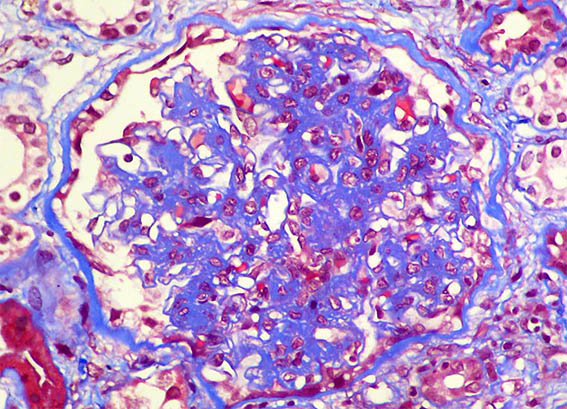

Figura 1. PAS, X400. Nódulos mesangiales.

Tricrómico de Masson, X400.